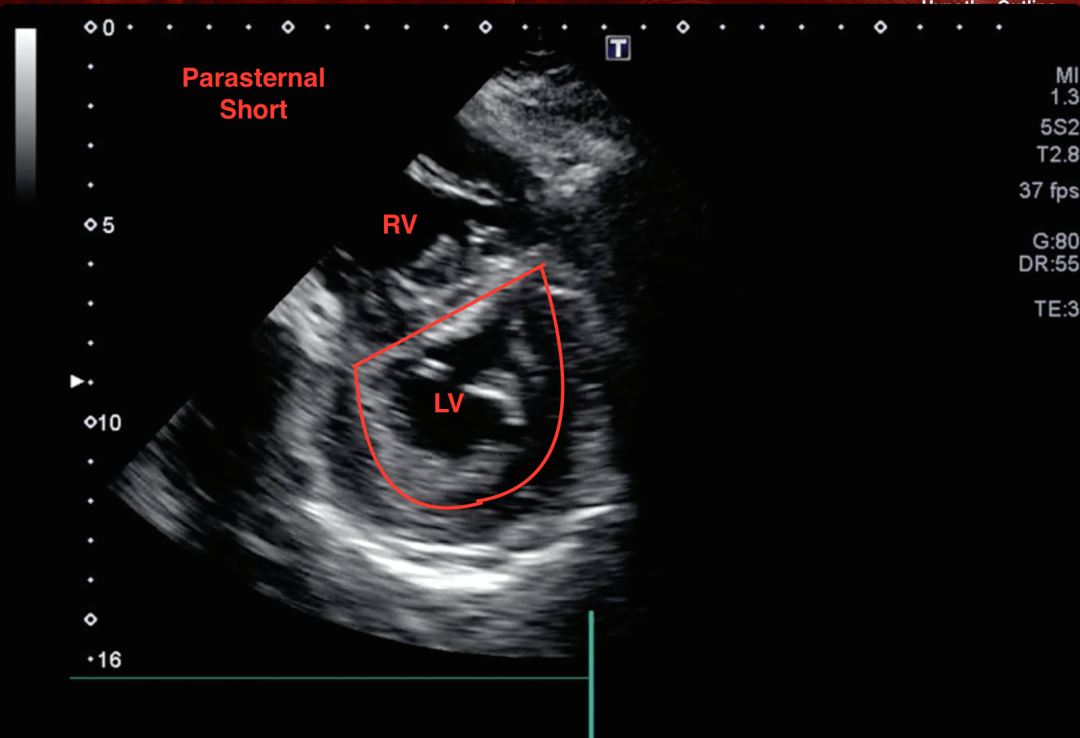

Here is a parasternal short view:

This is an impressive view because a d-sign is appreciated. A d-sign is an indication that the right-sided ventricular pressures are higher than the left ventricular pressures causing septal bowing. Wonder why it is called a d-sign? See below: